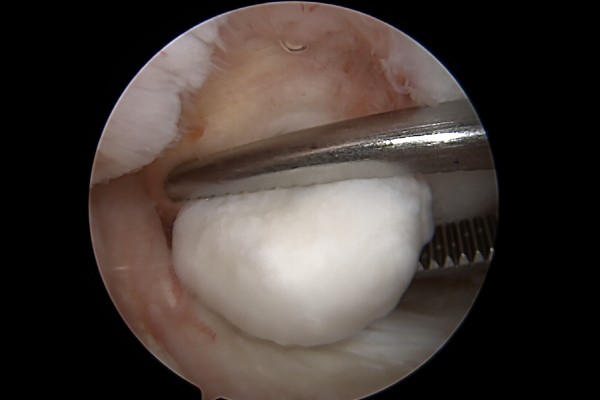

이를 수술도구로 제거하고,

깔끔하게 제거된 무릎 관절이 확인됩니다.